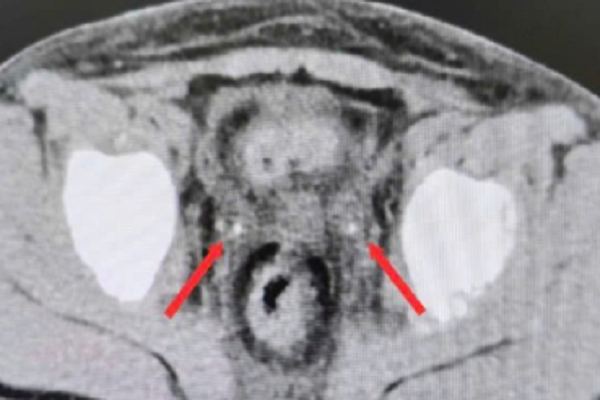

Kết quả CT scan bụng ghi nhận thận ứ nước hai bên, giãn niệu quản hai bên kèm sỏi kẹt đoạn cuối ở niệu quản hai bên, kích thước bên phải 3x7mm, bên trái 3x20mm.

Để tìm nguyên nhân gốc rễ, các bác sĩ chỉ định chụp CT scan bụng không cản quang. Kết quả chẩn đoán hình ảnh đã “giải mã” nguyên nhân gây suy thận: cả hai thận đều bị ứ nước do sỏi kẹt tại đoạn cuối niệu quản. Đáng chú ý, kích thước sỏi không hề nhỏ so với cơ thể trẻ em, với viên sỏi bên phải 3x7mm và bên trái lên tới 3x20mm.